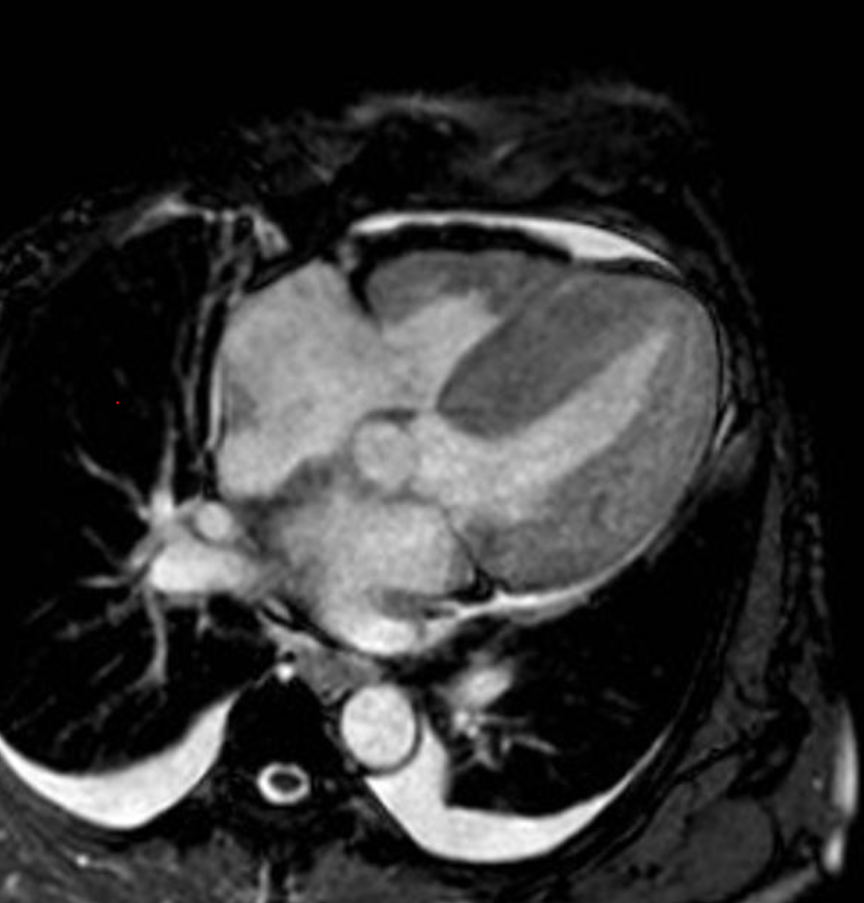

6) 심장 자기공명영상

출처 : https://radiopaedia.org/articles/restrictive-cardiomyopathy?lang=us

Restrictive cardiomyopathy | Radiology Reference Article | Radiopaedia.org

Restrictive cardiomyopathy is the least common subtype of cardiomyopathy and is characterized by a marked decrease in ventricular compliance. Clinical presentation Patients can present with symptoms and signs of left ventricular failure and/or...

radiopaedia.org

- 심장자기공명영상 : 민감도가 높은 검사법